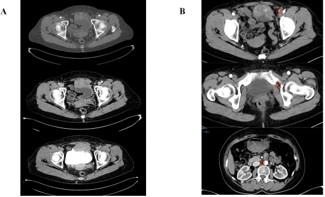

A 64-year-old woman presented with recurrent lower abdominal distension and discomfort for one week. After undergoing a pelvic CT scan, the results showed a lesion in the pelvis, a mass in front of the bladder, and it was considered to be a tumor with a high probability of malignancy (Figure 1A). The boundary between the lesion and the abdominal muscle on the front side was unclear, and there was a possibility of a vascular tumor thrombus on the left side (Figure 1B). There was a possibility of metastasis to multiple lymph nodes on the left side of the iliac external, obturator, and lateral branches of the aorta. In September 2024, due to the unclear nature of the lesion, we first performed a transurethral resection of the bladder lesion under general anesthesia to establish a definitive diagnosis and alleviate the patient’s sensation of abdominal distension. The postoperative pathological results indicated that it was a malignant spindle cell tumor of the bladder. The results of postoperative immunohistochemistry showed: UP3 (-), Myogenin (-), MyoD1 (-), CK (-), VIM (+), SMA (partially +), KI-67 (approximately 60% +), GATA3 (-), DESMIN (-). Two weeks later, the patient experienced urethral bleeding after urination without any obvious predisposing cause, accompanied by mild low back pain. After a comprehensive PET-CT examination, the results indicated a space-occupying lesion on the anterior wall of the bladder with increased metabolism, suggesting a tumor. It has not involved the gastrointestinal tract and there is no evidence of distant metastasis (Figure 2). In October 2024, a robotic-assisted laparoscopic radical cystectomy + ileal conduit operation was performed under general anesthesia. Intraoperatively, we identified this neoplasm originating from the anterior wall of the bladder, which was adherent to the abdominal wall muscles (Figure 3A). The neoplasm was large in size, grotesquely shaped, and soft in texture, resembling a cord-like structure of the intestine. It had invaded the extra-bladder fat, and tumor thrombi were found within the lumens surrounding the bladder. Upon postoperative examination of the specimen, the bladder measured approximately 8.0 x 9.0 x 2.5 cm in size. A cord-like mass measuring about 7.0 x 5.0 x 3.0 cm was visible on the anterior wall of the bladder, with a gray-brown cut surface that was soft in texture (Figure 3B). Upon repeat pathological analysis, the results unequivocally indicated that this is a malignant spindle cell tumor (Figure 3C). Immunohistochemistry indicated: CKH (-), CKL (-), EMA (-), CAM5.2 (-), VIM (+), SMA (+), CK5/6 (-), P40 (-), GATA-3 (-), Desmin (-), ALK (-), UP-3 (-), KI-67 20% (+), S-100 (-), CD34 (+), CD68 (+), ER (-), PR (-), SS18 (-), Calponin (-), MC (-), CR (-), WT-1 (-), CD10 (-), MDM-2 (-), CDK4 (-), CD117 (+), DOG-1 weakly (+), Caldesmon weakly (+), STAT6 (-) (Figure 2B). Combined with the results of immunohistochemistry, the specimen was consistent with extra-gastrointestinal stromal tumor (the maximum diameter of the tumor is approximately 7 cm, the mitotic figure is about 3 per 50 high-power fields, high risk grade).

Figure 1: (A) Pelvic CT scan reveals a mass on the anterior wall of the bladder, with CT images taken in the arterial phase, venous phase, and excretory phase from top to bottom. The mass is highly suspected to be a malignant tumor, with indistinct boundaries with the anterior abdominal muscles; (B) There is a possibility of multiple lymph node metastases in the left external iliac, obturator, and lateral branches of the aorta.